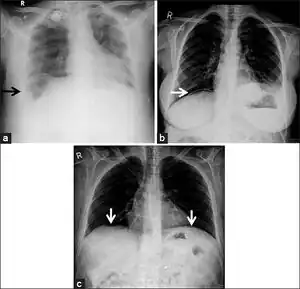

a) X-ray of abdomen, showing subdiaphragmatic free air, air outlining the properitoneal fat stripe black arrows b) Cupola sign arrowheads c) Rigler's sign d) chest radiograph showing free air under the diaphragms

a.b)Pneumoperitoneum developed three days following percutaneous radiologic gastrostomy